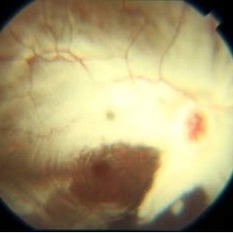

ARMD RPE Defect / Myelinated NFL

Jan 9 2014 by David Callanan, MD

ARMD RPE defect , myelinated nerve fiber layer in a 47-year-old male patient.

Condition/keywords: myelinated nerve fiber layer, retinal pigment epithelium (RPE) defect